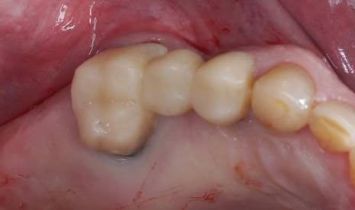

КЛинический случай Ильи коробкова

ранняя имплантация

Восстановление утраченного зуба 45 у возрастной пациентки.

✔️ В мягкую кость области зуба 45, удалённого незадолго до обращения, установлен агрессивный корневидный имплант Vega+

✔️ Через 4 месяца проведено протезирование керамической коронкой с трансокклюзионной фиксацией.

Для просмотра описания этапов лечения кликните по фото